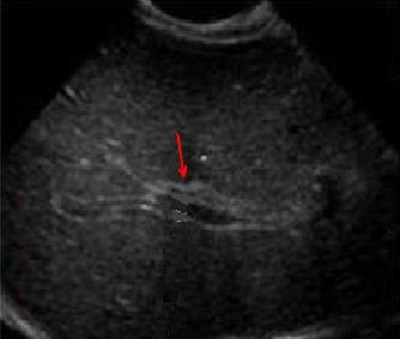

Image echographique de atresie de voie

biliaire est image de zone hyperechogene de forme

triangulaire ( signe de la corde triangulaire )

et image d'une formation kystique hilaire |

Atresie de voie biliaire :

Image de zone hyper-echogene en forme triangulaire (

signe de la corde triangulaire ) . Voie biliaire

intrahepatique et la vesicule biliaire sont moindre

de visible . |

Image echographique

percutanee : Meme cas en coupe longitudinale de voie

biliaire .( fleche rouge ). Epaissisement de la

paroi de voie biliaire hyperechoriche est tres

marquee |